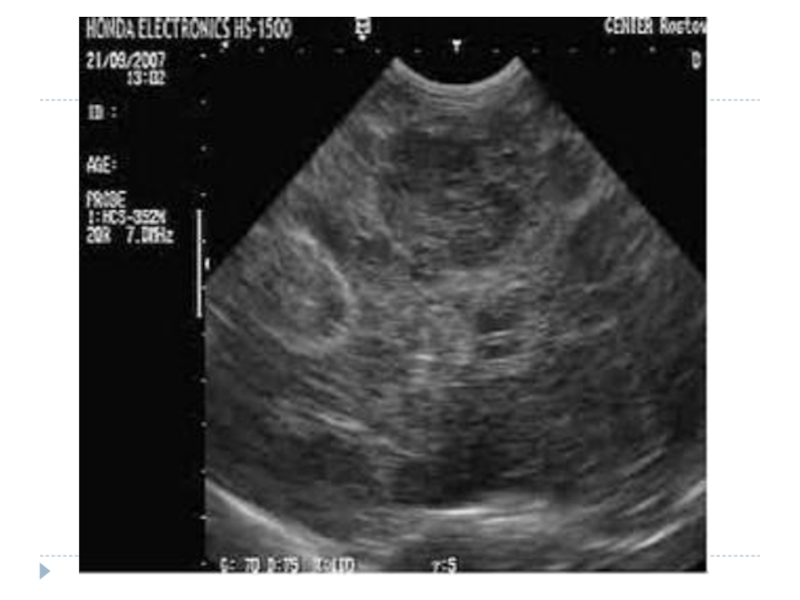

Ультразвуковое исследование (УЗИ) позволяет обнаружить опухоль и в некоторых случаях определить ее тип.

Обязательные методы исследования Ультросонография + прицельная аспирационная тонкоигольная биопсия. Ангиографию печени выполняют после введения контрастного вещества в чревной ствол; Компьютерная томография; Ядерно-магнитный резонанс

Компьютерная томография (КТ) очень эффективна при диагностике опухолей печени, позволяет обнаружить даже маленькие новообразования, незаметные на УЗИ. В ЛIСОД для улучшения изображения проводится КТ с контрастированием – внутривенно вводится контрастное вещество, что дает возможность специалистам изучить расположение сосудов в печени. Во время компьютерной томографии аппарат получает изображение тонких срезов, что позволяет специалистам тщательно обследовать структуру органа и выявить даже небольшие опухоли.